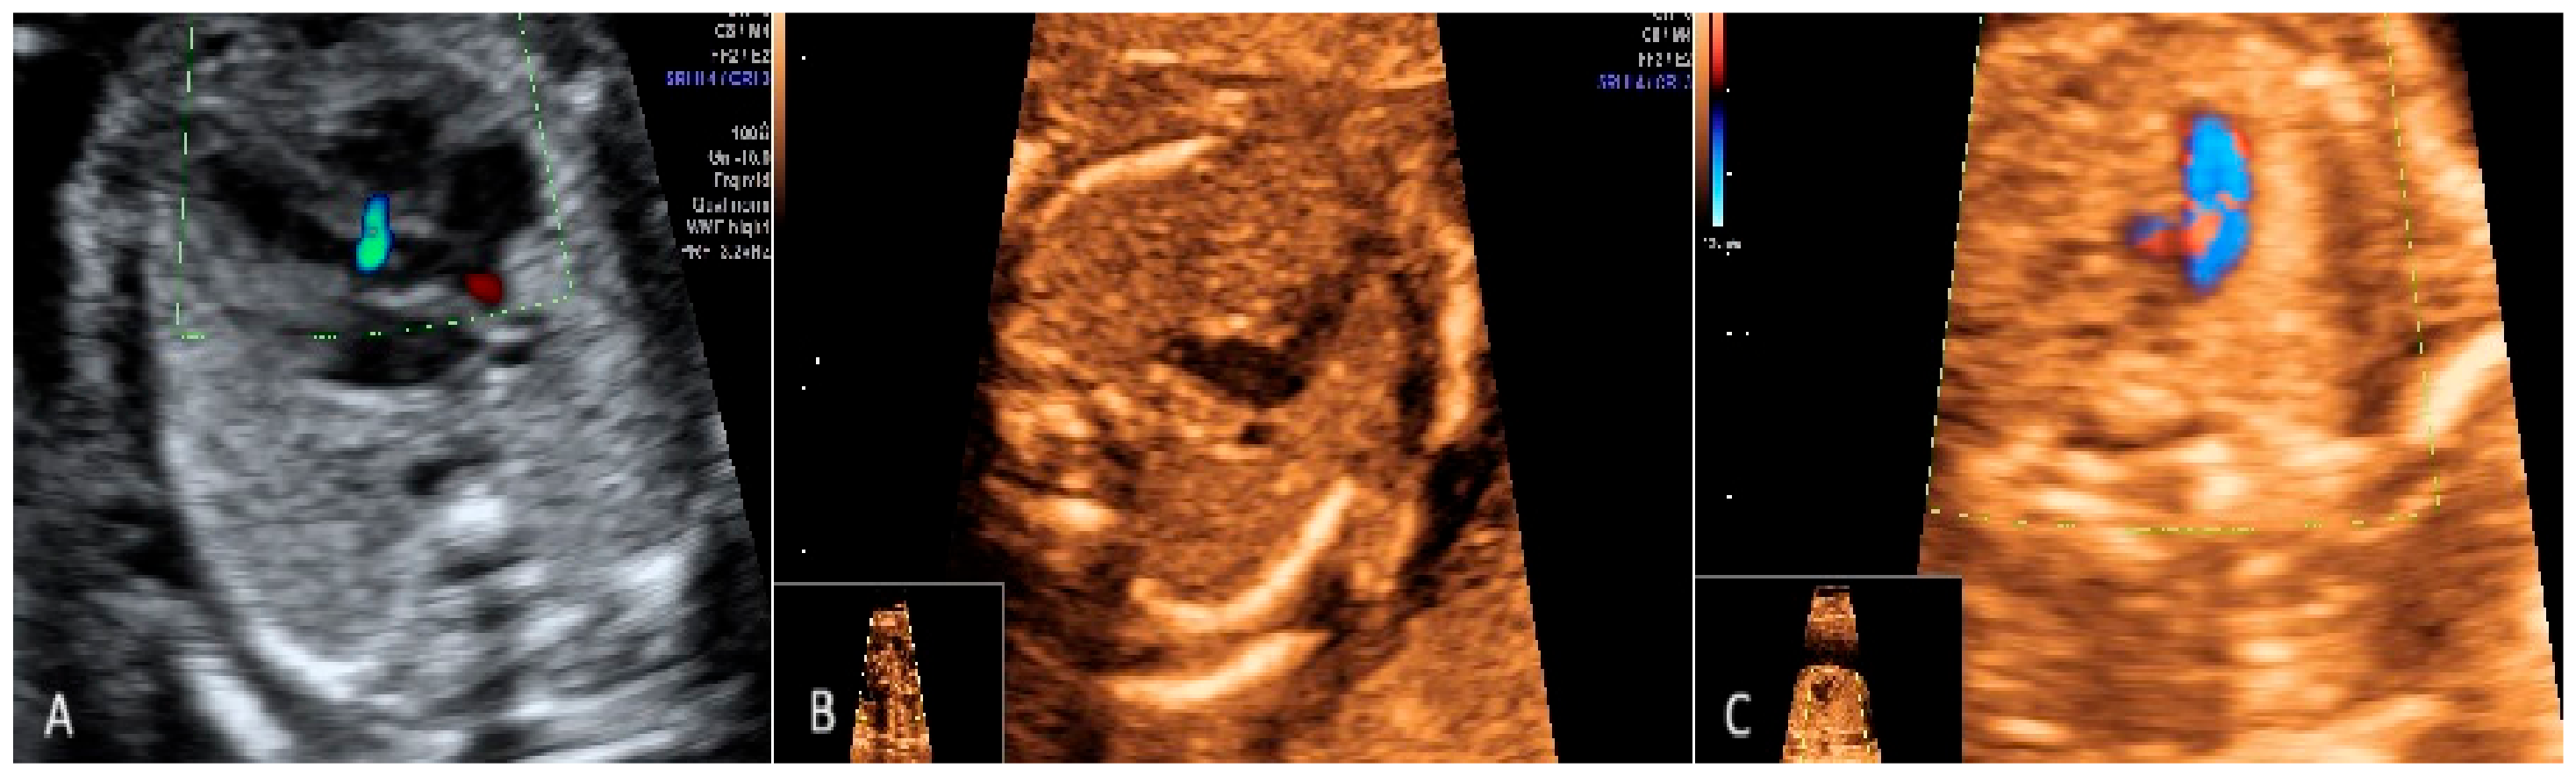

2.1. First Trimester Scanning and Sections

3.1. First-Trimester Evaluation